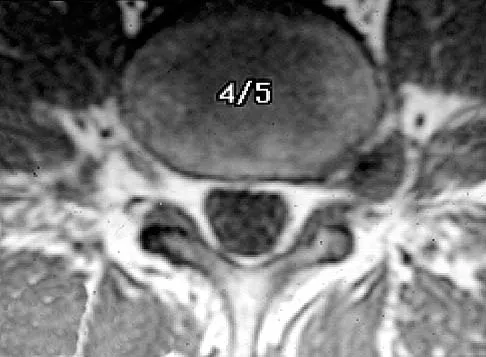

Figures 27a and 27b show the radiographs of a 32-year-old woman who was involved in a high-speed motor vehicle accident. She is neurologically intact. After stabilization and assessment, treatment should consist of

Explanation

The radiographs show a fracture-dislocation with translation in both the coronal and sagittal planes, evidence of significant instability requiring surgical stabilization. Anterior instrumentation is not as effective as posterior instrumentation in restoring stability, and because there is little bony destruction, the anterior column can be successfully reconstructed with simple realignment. The treatment of choice is multisegment posterior fusion with instrumentation. Lewandrowski KU, McLain RF: Thoracolumbar fractures: Evaluation, classification, and treatment, in Frymoyer JW, Wiesel SW (eds): The Adult and Pediatric Spine. Philadelphia, PA, Lippincott Williams and Wilkins, 2004, pp 817-843.